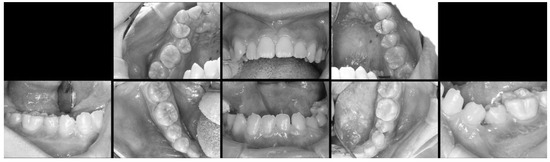

The treatment was carried out under general anesthesia with the aim of improving his oral hygiene. Initial observation of his oral condition was carefully completed. Dental X-ray and intraoral images during the administration of analgesic were obtained before starting the surgery (Figure 2 and Figure 3). A local anesthetic, proparacaine hydrochloride/felypressin (Citanest-Octapressin Cartridge for Dental use®), was injected into the affected area. An incision was made around the area along the cervical region and the oral mucosa was removed, which revealed the concealed tooth. It was observed from the left buccal side, but it was considered to be partially ankylosed. Then, a part of the target tooth was histopathologically examined to determine if there was any sign of ankylosis around it. Eventually, the tooth was divided into parts for smooth extraction, and the incision was closed using absorbable sutures (Figure 4).

Figure 4. Condition of the target tooth during oral surgery. The target tooth was visible after removal of the oral mucosa, and the tooth was divided into two parts and extracted.